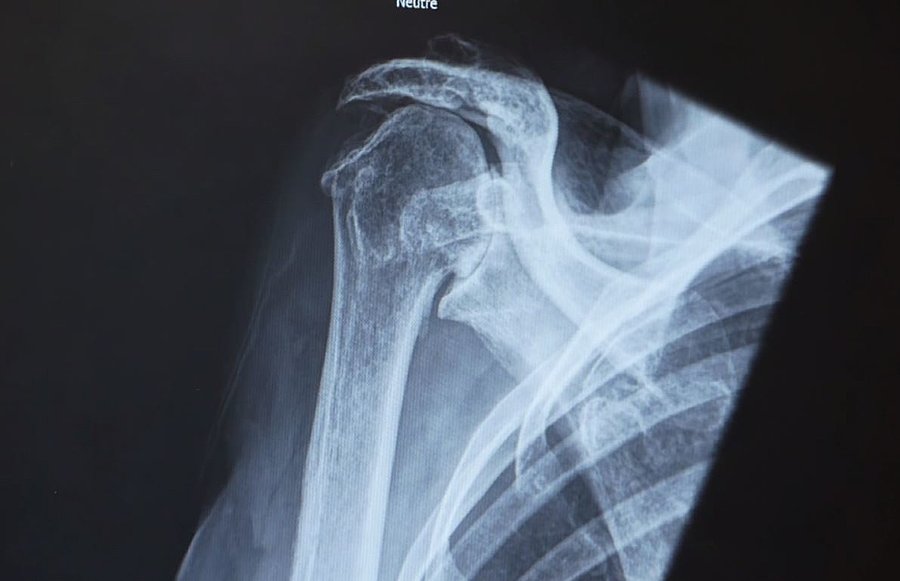

Notre équipe de chirurgiens orthopédistes, de chirurgien plastique reconstructrice, de physiothérapeutes est spécialement formée pour traiter une gamme complète de conditions liées à l'épaule, au coude et au membre supérieur. Que ce soit pour des blessures sportives, des troubles dégénératifs ou des traumatismes, nous offrons des solutions adaptées à chaque individu.

À Morges, il crée un registre clinique regroupant plus de 400 prothèses d’épaule et mène un PhD (recherche approfondie universitaire) sur l’optimisation des prothèses inversées. Il réalise plus de 350 chirurgies annuelles, notamment :

• Prothèses d’épaule pour arthroses, états dégénératifs et fractures (>70/an)

• Stabilisations pour luxations de l’épaule (>30/an)

• Réparations arthroscopiques de la coiffe des rotateurs (>100/an)